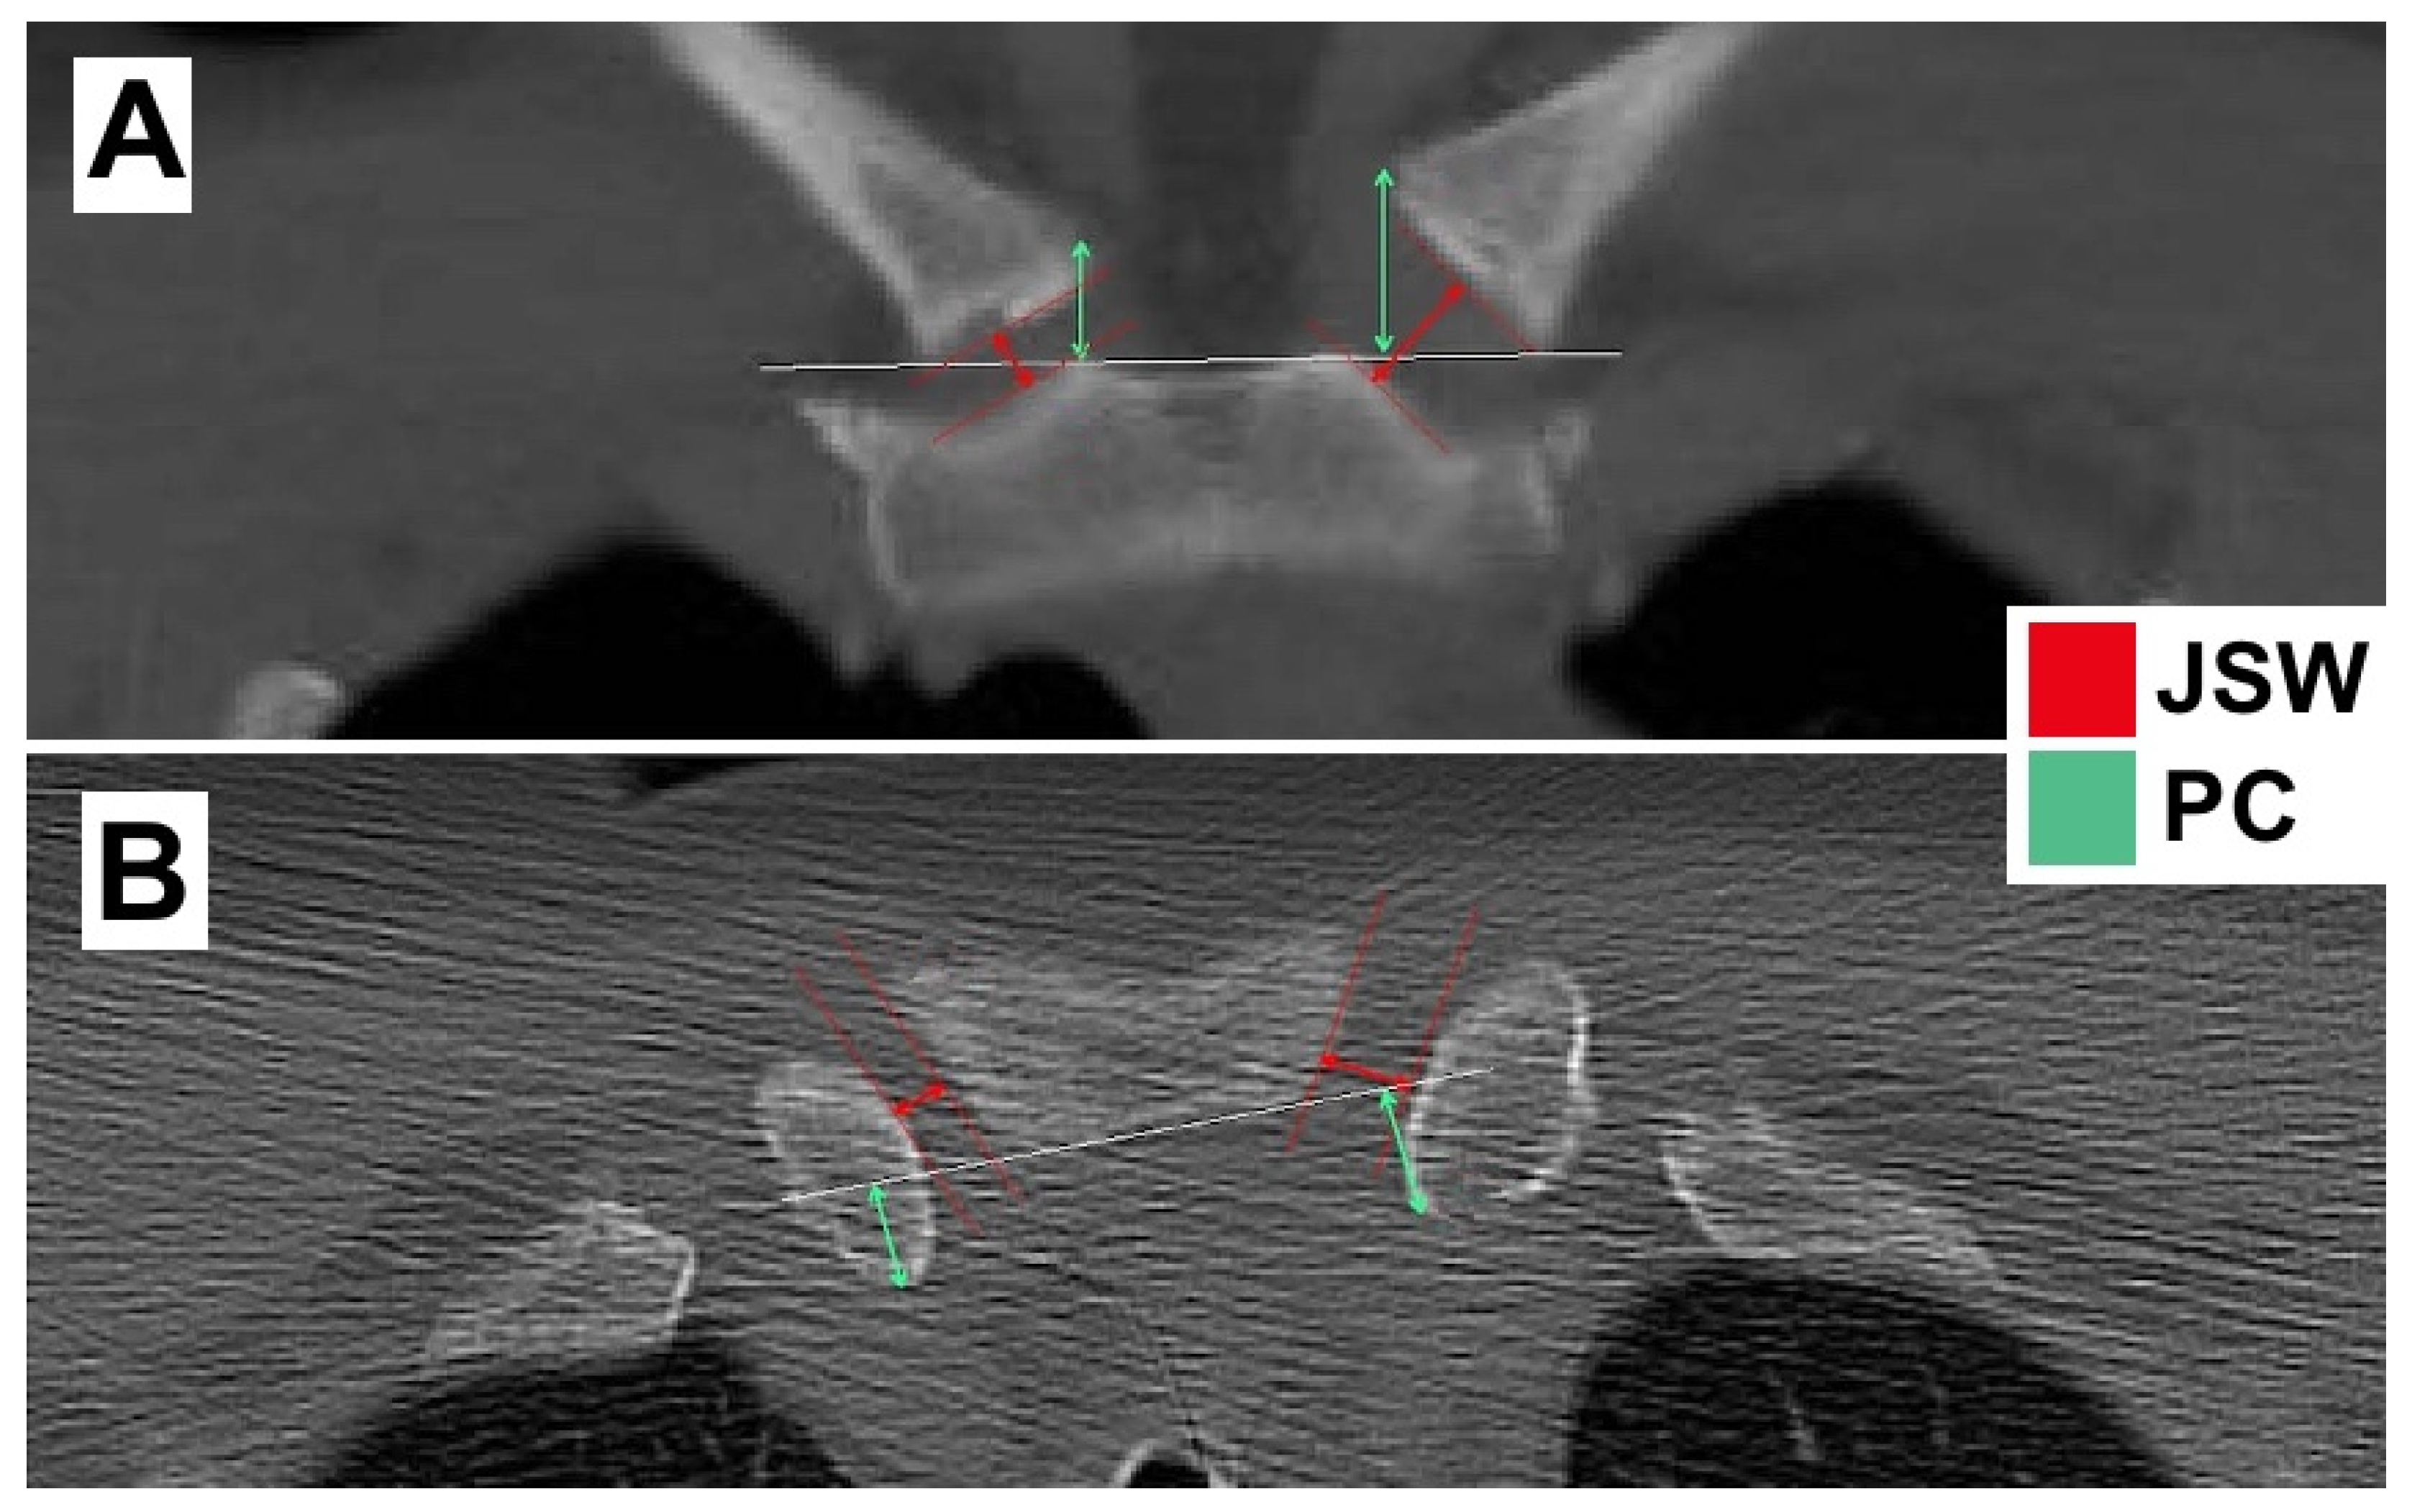

2.2. Radiological Evaluation

| cJSW | aJSW | cPC | aPC | |

|---|---|---|---|---|

| Affected side in mm | 8.70 (4.30–15.50) | 8.98 (4.50–4.10) | 14.31 (5.50–31.30) | 9.40 (2.20–14.40) |

| Non-affected side in mm | 7.63 (3.40–13.40) | 8.32 (4.10–13.20) | 13.49 (4.90–22.40) | 9.02 (1.00–9.02) |

| Mean difference in mm | 1.07 (1.67) | 0.67 (2.02) | 0.83 (2.07) | 0.38 (2.20) |

| Mean difference in % | 14.02 m | 7.93 m | 6.08 m | 4.02 m |

| p-value | <0.001 | 0.044 | 0.011 | 0.274 |